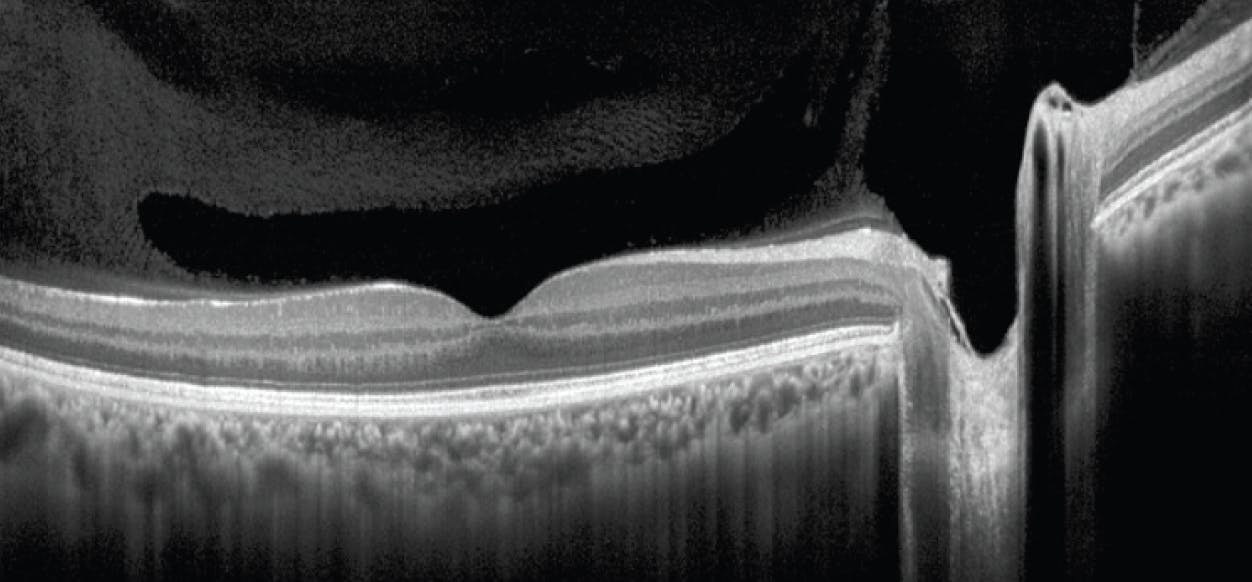

As PVDs evolve, residual cortical vitreous tissue may be left on the surface of the retina. Proliferation of this cortical vitreous debris can proliferate, resulting in ERM formation. ERMs are sheet-like membranes that develop superficially to the ILM of the retina (Figure 3). These structures are made up of glial cells and laminocytes (histiocytes), which expand and contract, resulting in anatomic changes (distortion) to the ILM.9 Traction imposed by the ERM can result in thickening of the underlying retina. Patients with ERM can be observed unless they are experiencing diplopia, metamorphopsia, or if their vision is 20/60 or less. It is appropriate to refer these patients to a retina specialist for possible intervention, including membrane peel with vitrectomy.10